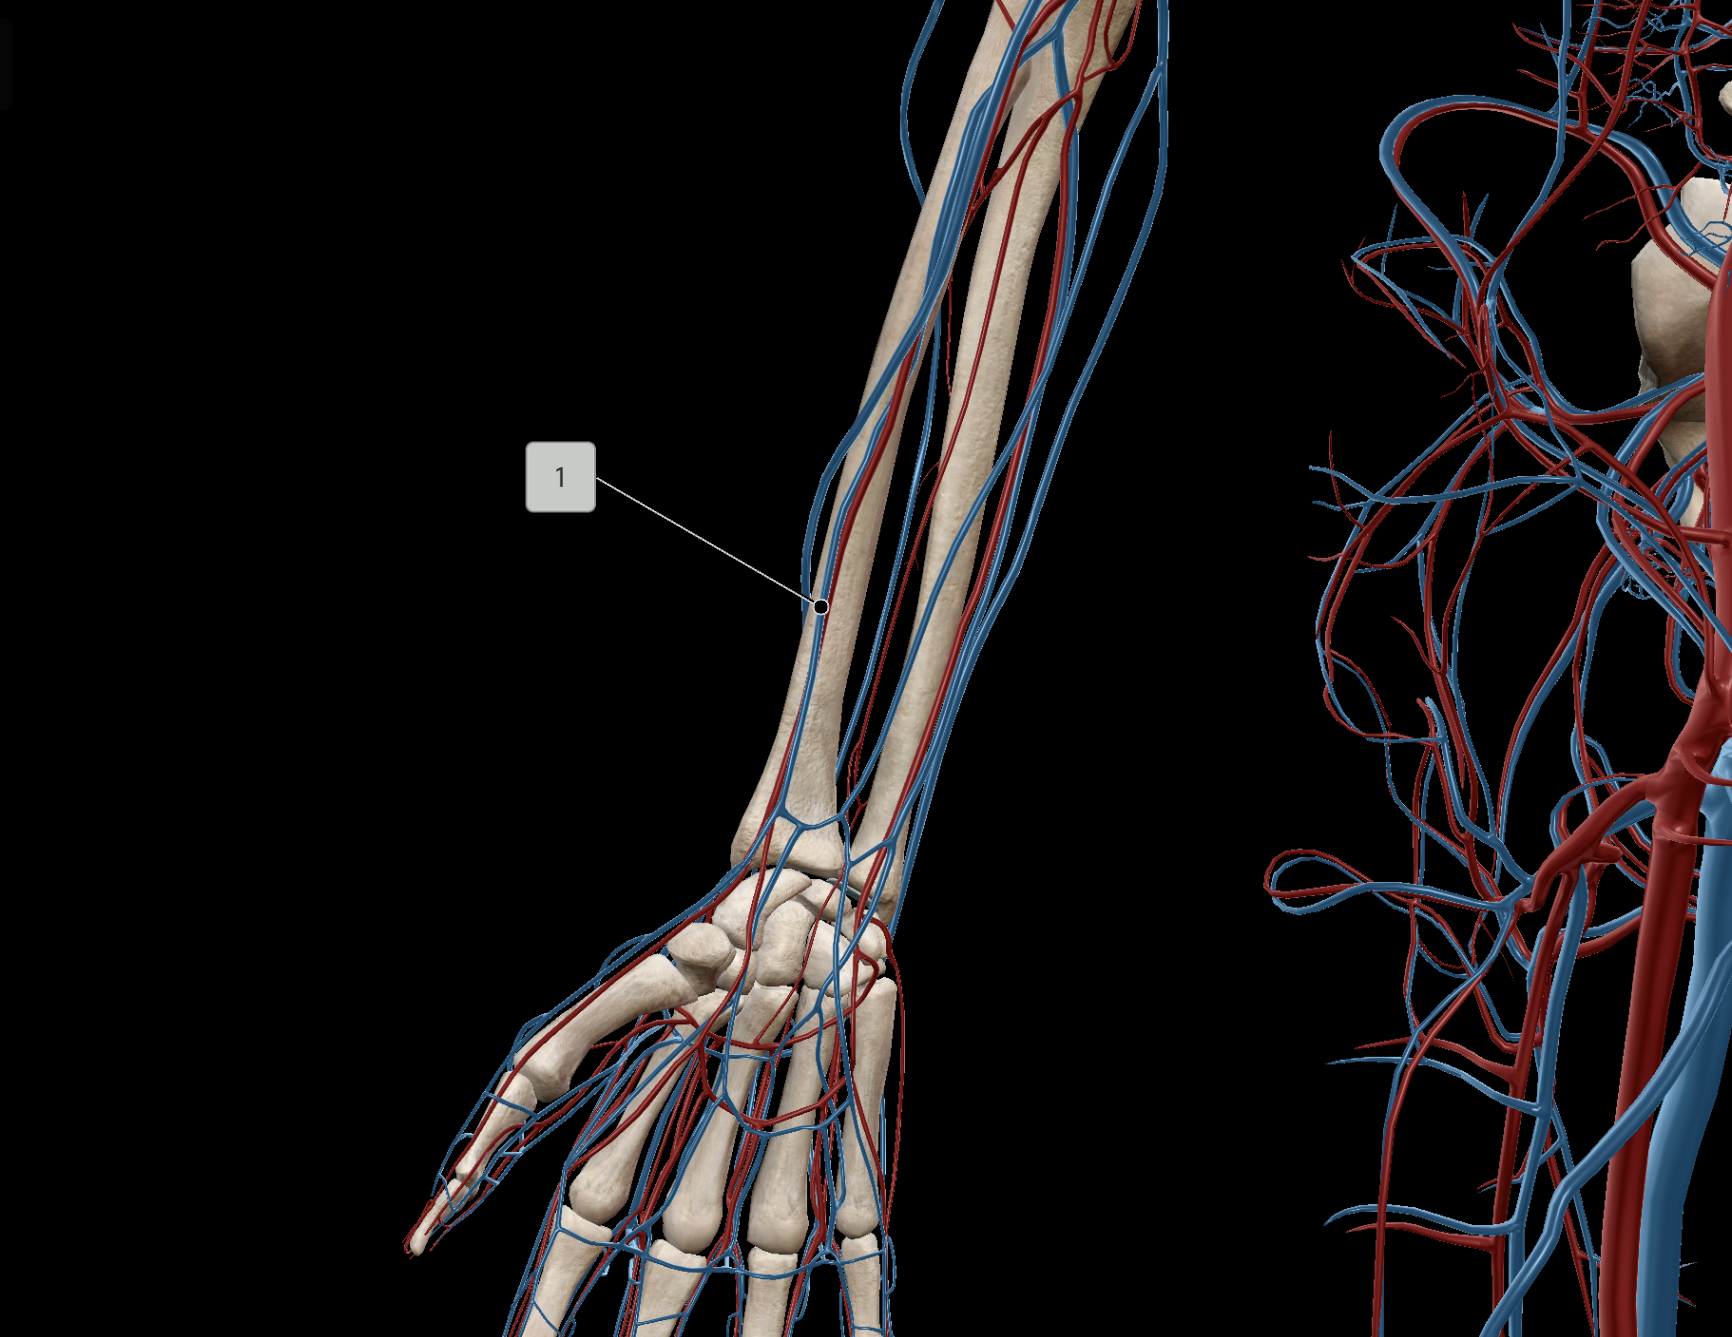

Brachial Vein

Radial Vein

Ulnar Vein

Ulnar Artery

Radial Artery